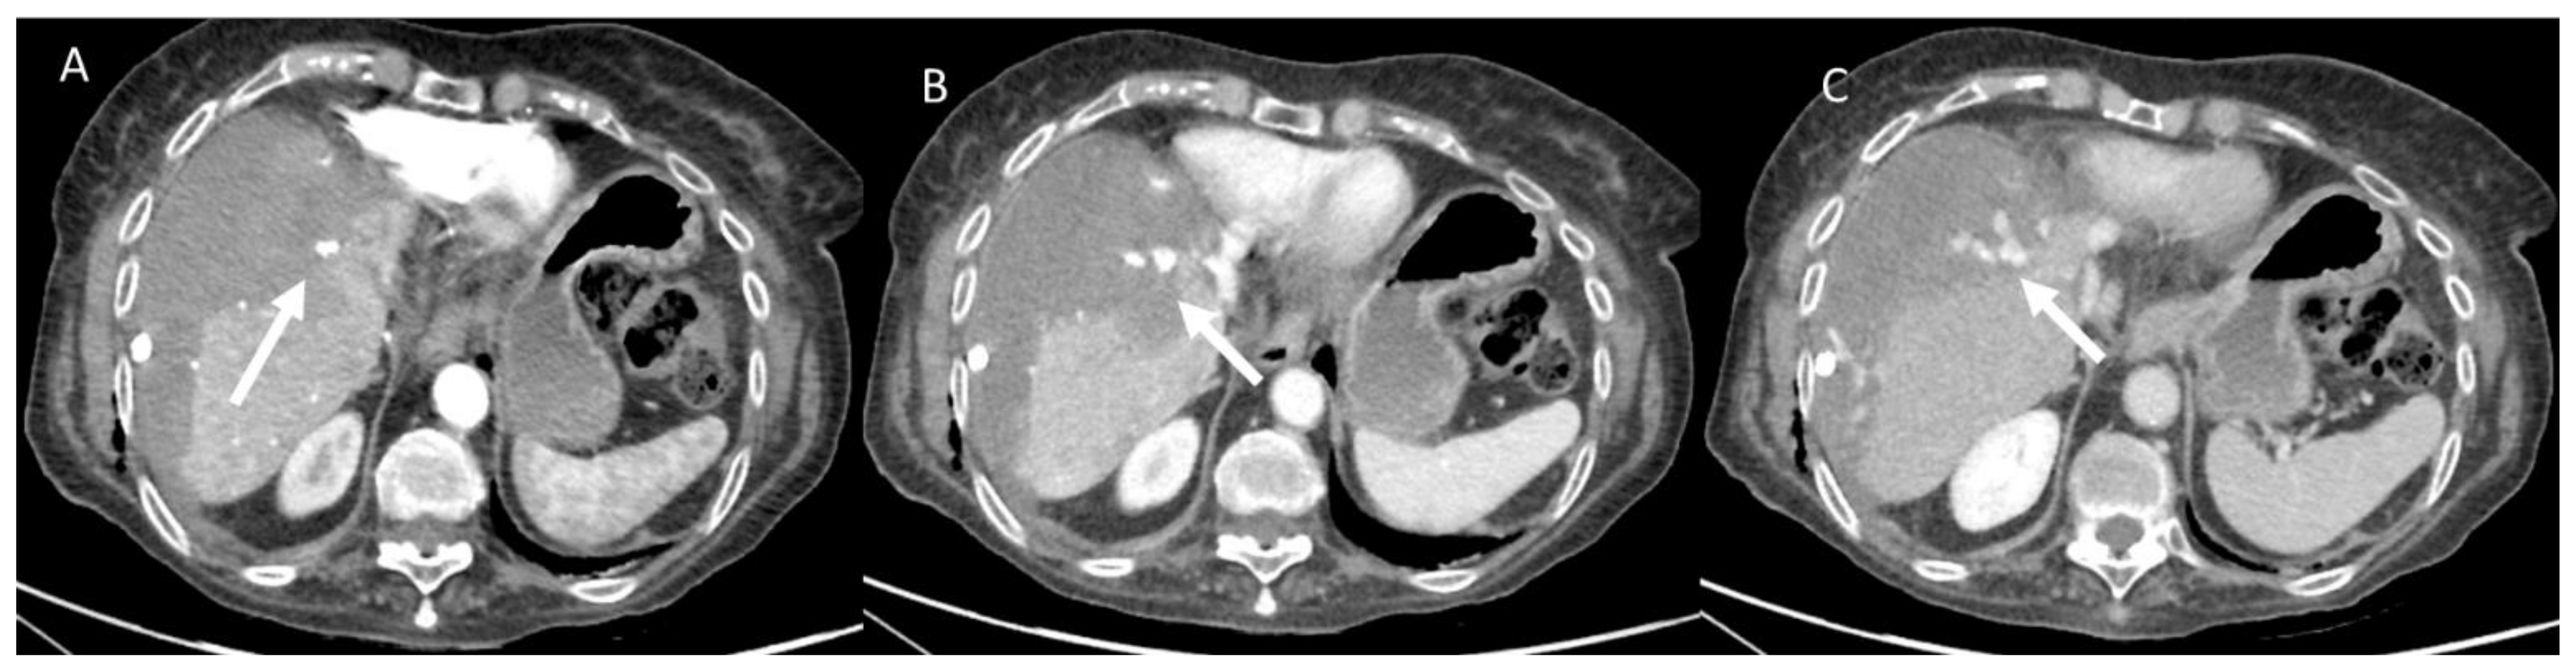

- Granata, V.; Grassi, R.; Fusco, R.; Belli, A.; Cutolo, C.; Pradella, S.; Grazzini, G.; La Porta, M.; Brunese, M.C.; De Muzio, F.; et al. Diagnostic evaluation and ablation treatments assessment in hepatocellular carcinoma. Infect. Agents Cancer 2021, 16, 53. [Google Scholar] [CrossRef] [PubMed]

- Izzo, F.; Granata, V.; Grassi, R.; Fusco, R.; Palaia, R.; Delrio, P.; Carrafiello, G.; Azoulay, D.; Petrillo, A.; Curley, S.A. Radiofrequency Ablation and Microwave Ablation in Liver Tumors: An Update. Oncologist 2019, 24, e990–e1005. [Google Scholar] [CrossRef] [Green Version]